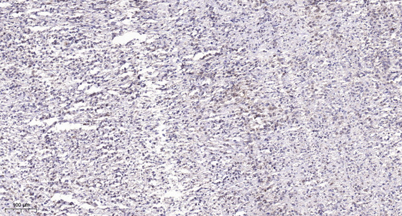

Product name: TCF-1 rabbit pAb

Dilutions: Western Blot: 1/500 - 1/2000. Immunohistochemistry: 1/100 - 1/300. ELISA: 1/10000. Not yet tested in other applications.